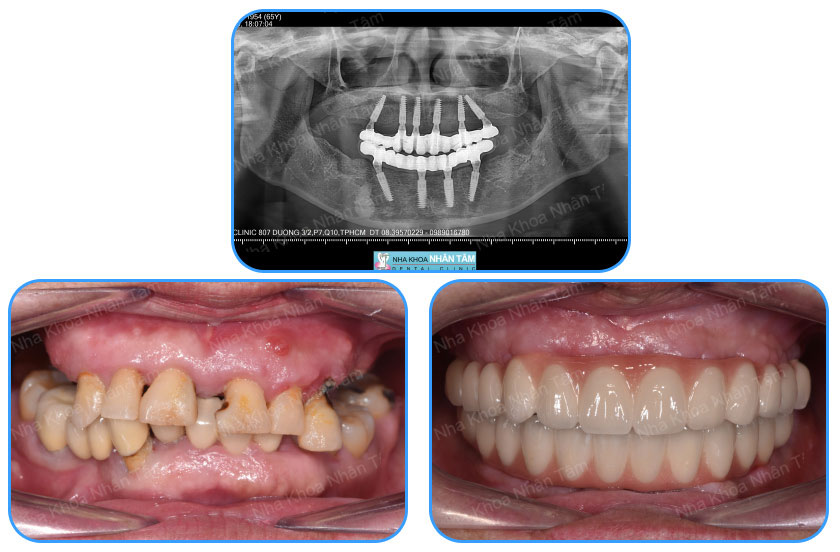

Khách hàng thực hiện cấy ghép Implant All on 4

Bước 2: Kiểm tra sức khỏe răng miệng, chụp Xquang để kiểm tra cấu trúc xương.